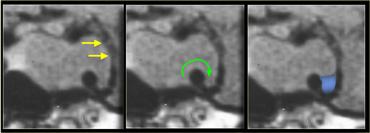

Một hướng lan rộng phổ biến khác là sang bên vào xoang hang (cavernous sinus).

Không phải lúc nào cũng có thể xác định được có xâm lấn xoang hang hay không, nhưng có ba dấu hiệu cần chú ý:

– Có hơn 50% chu vi động mạch cảnh bị bao quanh không? Lưu ý: u màng não có xu hướng làm hẹp động mạch cảnh, trong khi u đại tuyến thì không.

– Có sự dịch chuyển ra ngoài của thành bên xoang hang so với bên đối diện không?

– Có sự gia tăng lượng mô xen giữa động mạch cảnh và thành bên xoang hang không?